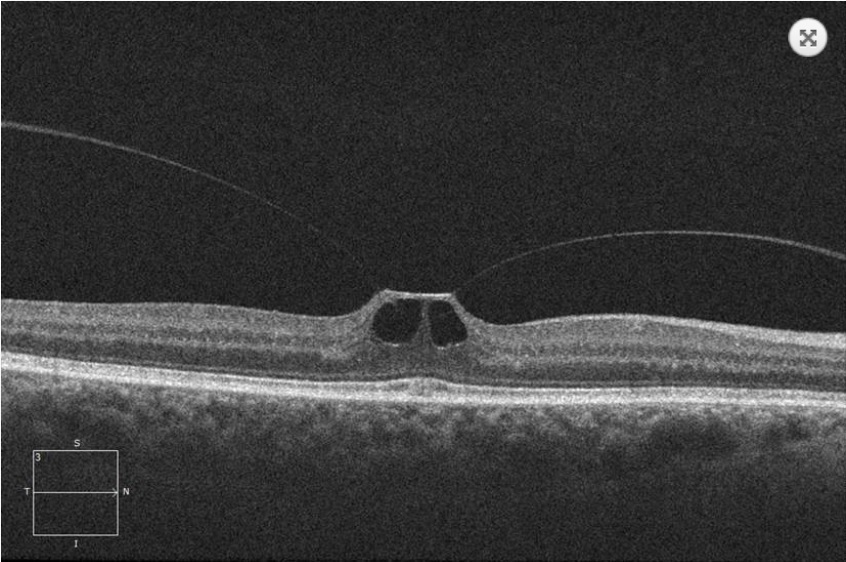

O que é a Síndrome de Tração Vítreomacular?

- DVP parcial, com forte adesão na região macular, associada a tração nesta região, distorcendo a arquitetura local.

Qual é a classificação da STVM?

Adesão Vítreomacular: sem distorção da arquitetura macular

STVM Focal: adesão menor 1500 micrômetros

STVM Difusa: adesão maior 1500 micrômetros